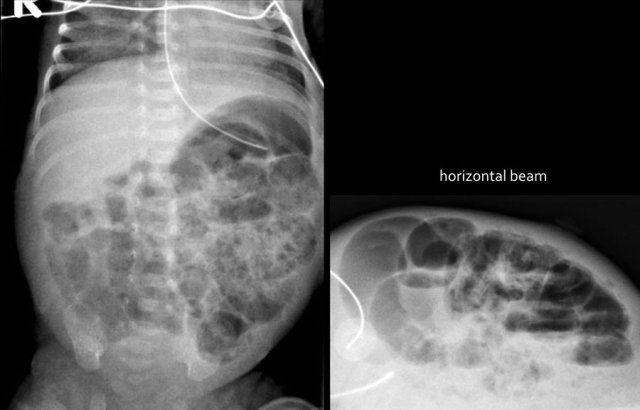

The images show a typical case of NEC with pneumatosis intestinalis.

On the horizontal beam image there is no sign of free air.

Here images of a neonate who developed NEC.

At this early stage the radiograph only shows non-specific bowel dilatation.

At this stage you cannot make the diagnosis.

The findings are:

- Multiple dilated small bowel loops

- Pneumatosis intestinalis.

- Pneumoperitoneum.

Diagnosis:

NEC with perforation.